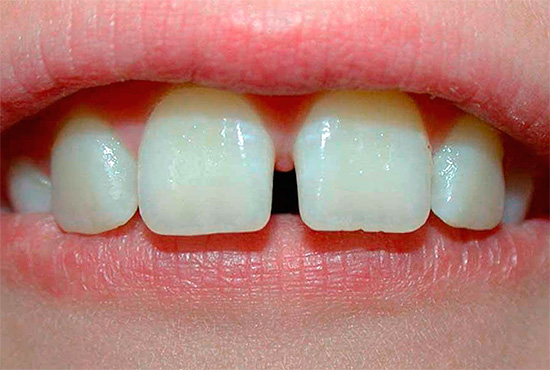

- Il diastema mediano è il divario tra i primi incisivi della mascella superiore. In un morso precoce intermittente (da 2,5 a 4,5 anni), un diastema è una normale condizione fisiologica quando il frenulo del labbro superiore passa tra incisivi centrali temporanei. Con lo sviluppo normale durante l'eruzione degli incisivi e delle zanne laterali, questo divario si chiude e l'attacco del frenulo viene spostato e intrecciato nella mucosa del labbro superiore. In alcuni casi, la causa del diastema può essere la presenza di un dente soprannumerario nell'area della discrepanza dei denti centrali della mascella superiore (questa patologia può essere identificata dai risultati di un esame radiografico).